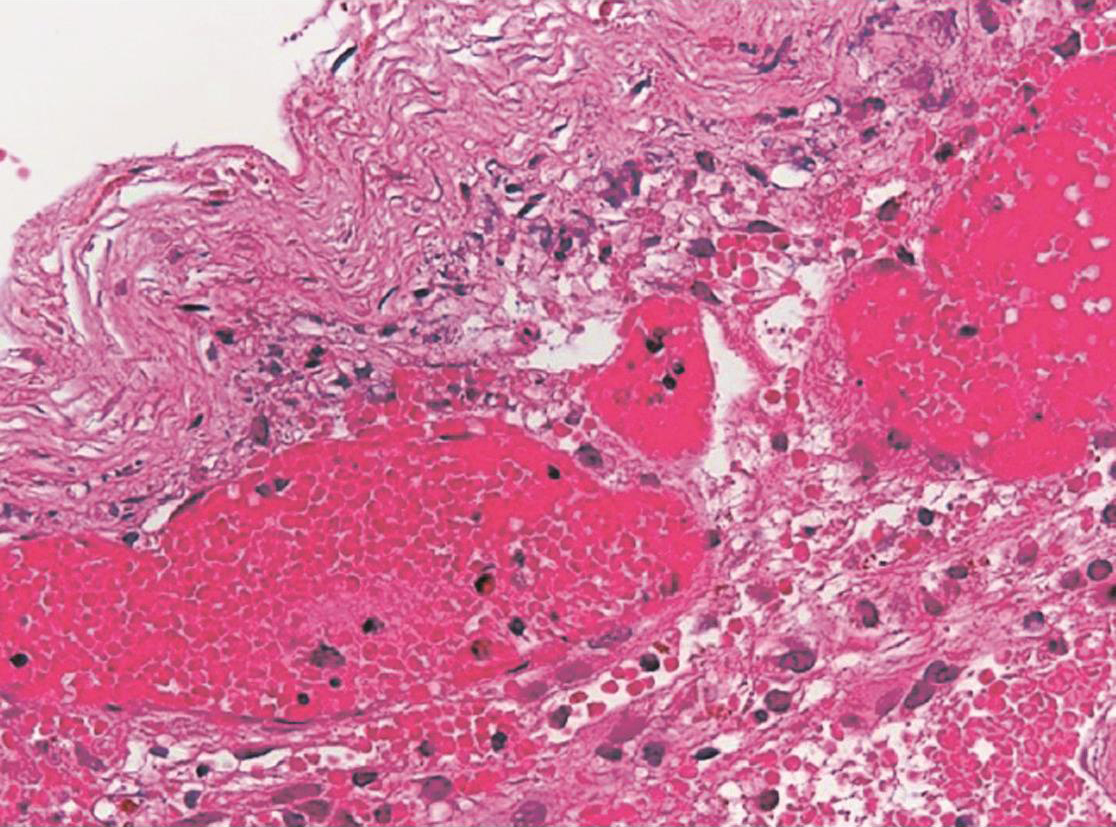

脑内血肿颅内高压:明显的头痛、恶心、呕吐及生命体征变化等。局灶性症状:额叶底部和颞叶前部脑内血肿,常伴有严重的脑挫裂伤和脑干损伤,多呈持续昏迷状态。若血肿破入脑室,患者意识障碍更加明显;位于运动区附近的血肿,可出现偏瘫、失语和局灶性癫痫。顶叶血肿可出现偏侧感觉障碍。脑疝的症状:瞳孔散大、反应消失,意识障碍和生命体征改变。脑内血肿与损伤时的着力点有关,头侧方着力发生脑内血肿较枕部、前额着力多见,在侧方着力中以着力同侧的脑内血肿较对侧部位为多见,据统计脑内血肿以颞叶最多,额叶次之,顶叶少见,枕叶和小脑更少见(图2-4-1)。

图2-4-1 颅内血肿-硬膜外血肿病理表现

脑内血肿颅内高压:明显的头痛、恶心、呕吐及生命体征变化等。局灶性症状:额叶底部和颞叶前部脑内血肿,常伴有严重的脑挫裂伤和脑干损伤,多呈持续昏迷状态。若血肿破入脑室,患者意识障碍更加明显;位于运动区附近的血肿,可出现偏瘫、失语和局灶性癫痫。顶叶血肿可出现偏侧感觉障碍。脑疝的症状:瞳孔散大、反应消失,意识障碍和生命体征改变。脑内血肿与损伤时的着力点有关,头侧方着力发生脑内血肿较枕部、前额着力多见,在侧方着力中以着力同侧的脑内血肿较对侧部位为多见,据统计脑内血肿以颞叶最多,额叶次之,顶叶少见,枕叶和小脑更少见(图2-4-3)。

图2-4-3 颅内血肿-脑内血肿病理表现